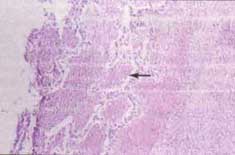

Figura No. 1 Vista panorámica del pulmón.

Se observan los cambios necróticos extensos, con preservación de algunos septos alveolares y depósito de abundante material fibrinoide eosinofílico (flecha), (H/E, 10x).